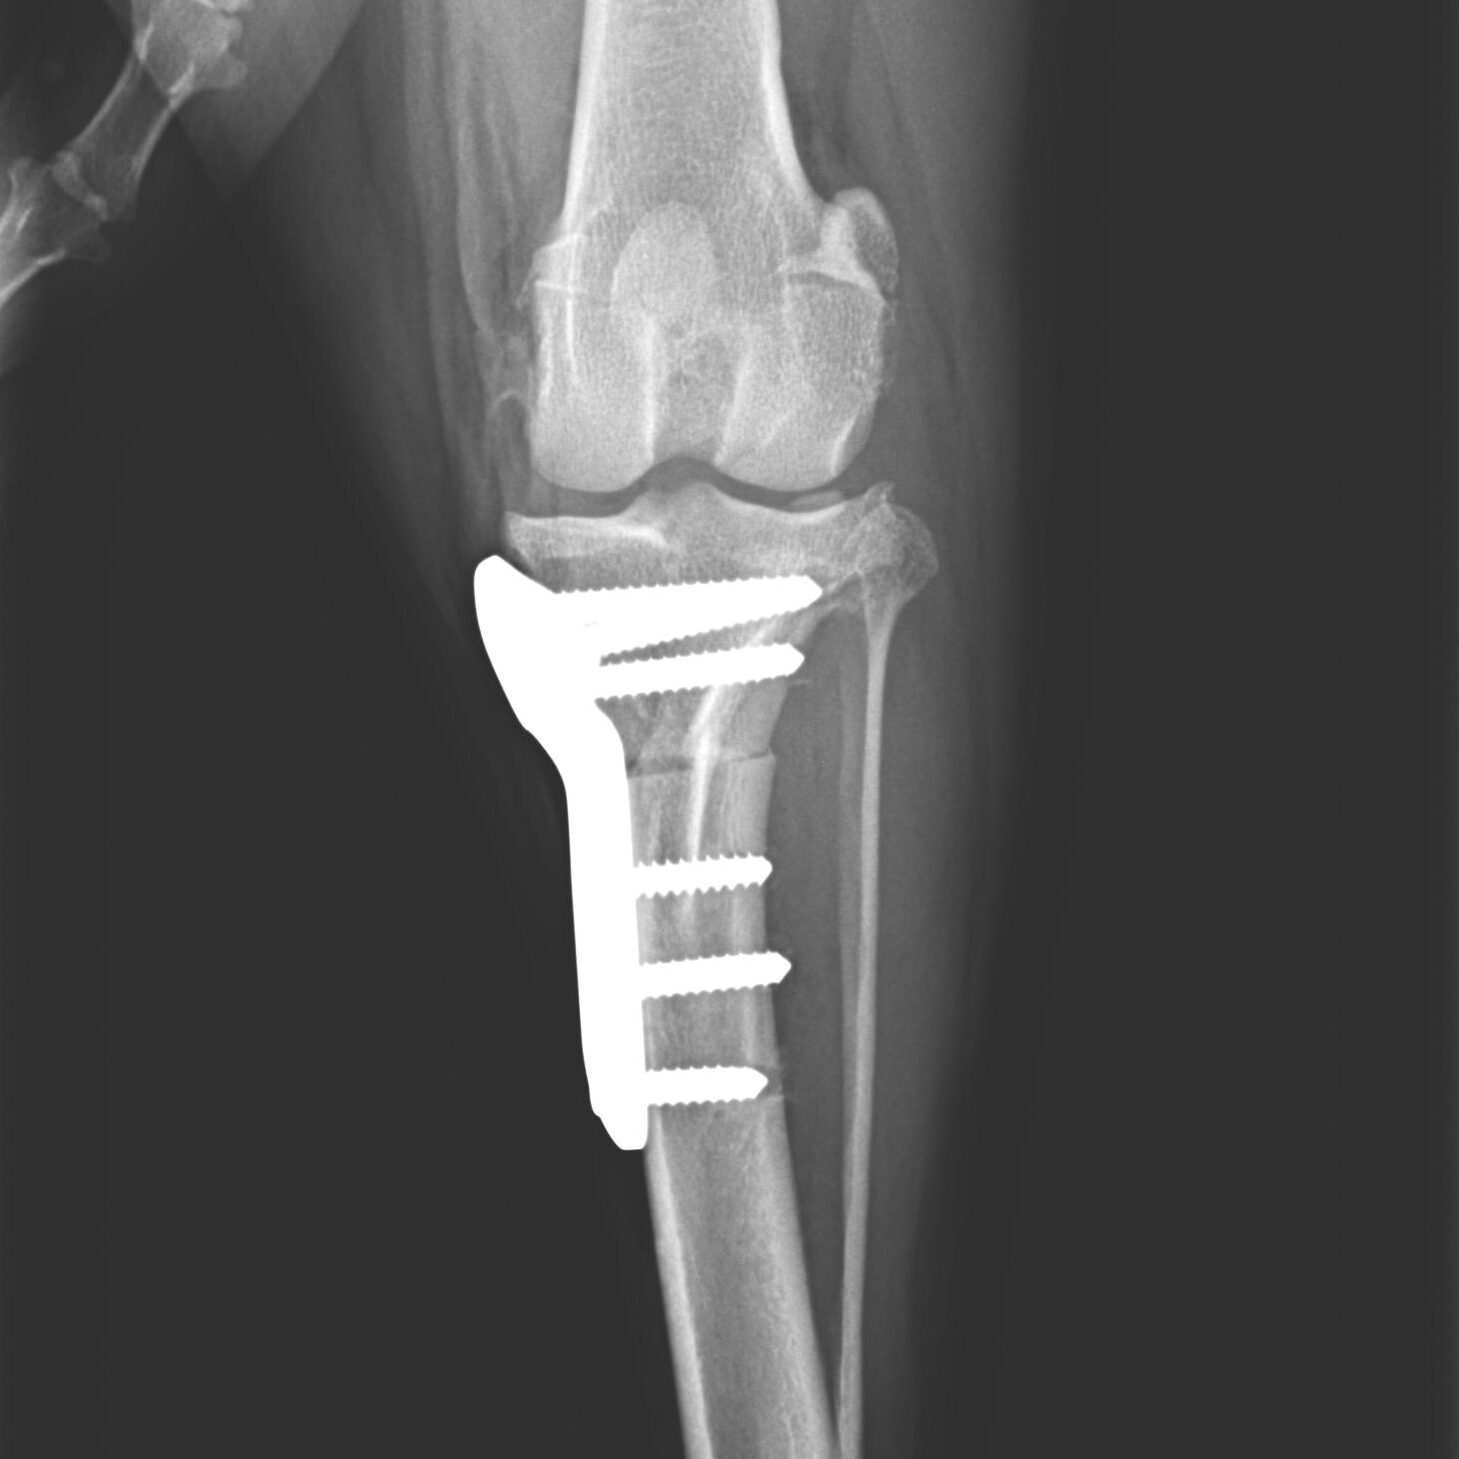

Knochenchirurgie

- Frakturversorgung, Korrekturosteotomie, u.a., verschiedenste Methoden wie Fixateur externe, interne Implantationen von Drähten, Nägeln, Schrauben, Platten inklusive SOP u.a.

Gelenkchirurgie inklusive Arthroskopie

- Kreuzbandriss, Meniskusläsionen, Patellaluxation, laxe Schulter, Isolierter Processus anconaeus, Fragmentierter Processus coronoideus, Osteochondrosis dissecans, Luxationen, Frakturen u.a.